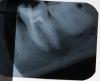

Wella Опубликовано 7 августа, 2013 Поделиться Опубликовано 7 августа, 2013 Добрый вечер! Помогите, пожалуйста, советом, какой зуб удалять - 7 или 8. У меня драма в трех частях1) Два месяца назад начал с болями резаться нижний правый зуб мудрости, у хирурга сделали иссечение капюшона, в следующие пару дней стремительно развился острый гнойный периостит, щека сильно раздулась. Доктор сделал разрез (вышло много гноя), назначил антибиотики и отпустил. Сказал при этом, что на соседнем 7м зубе кистогранулема и он в будущем на удаление. Сам 8й растущий зуб здоров.2) Через несколько дней после прекращения антибиотиков случился рецидив - пульсирующая боль между 7 и 8м, сильная опухоль щеки. Разрез не делали, назначили новый антибиотик, в течение недели отек спал и боль стихла.3) Еще через пару недель, вот сейчас - снова рецидив. Пульсирующая боль между 7 и 8м, щека медленно опухает, никакие таблетки уже не берут, ни найз, ни кетанов, не сплю совсем Сегодня сделали надрез и поставили дренаж, гноя мало, антибиотик пока не назначен. В пятницу надо принять решение, что удалять. Я рассчитывала на удаление 8-ки - по моим ощущениям, она растет в бок 7ке, и от этого место стыка болит. И вообще зуб мудрости - вещь бесполезная, рано портящаяся, и неизвестно, сколько еще раз он будет расти с такой вот болью. Для основы под мост не пригоден - растет не в ряду (см на фото)А доктор говорит, что она бы удалила 7ку. Он хорошо пролечен, но киста под ним - источник инфекции, из-за этого скорее всего и случается мой периостит. Сам зуб с виду хороший, но в десне слегка пошатывается. На свежем снимке видно, что у него под корнями. И теоретически 8й может встать на место удаленного го в ряд. Но ведь если удалить 7й, 8й продолжит с болями прорезываться? Мне уже страшно надоела постоянная боль и эта щека, и антибиотики, хочется решить уже раз и навсегда этот вопрос. Но не удалять же их оба сразу?Какой вам кажется более целесообразно убрать? Ссылка на комментарий